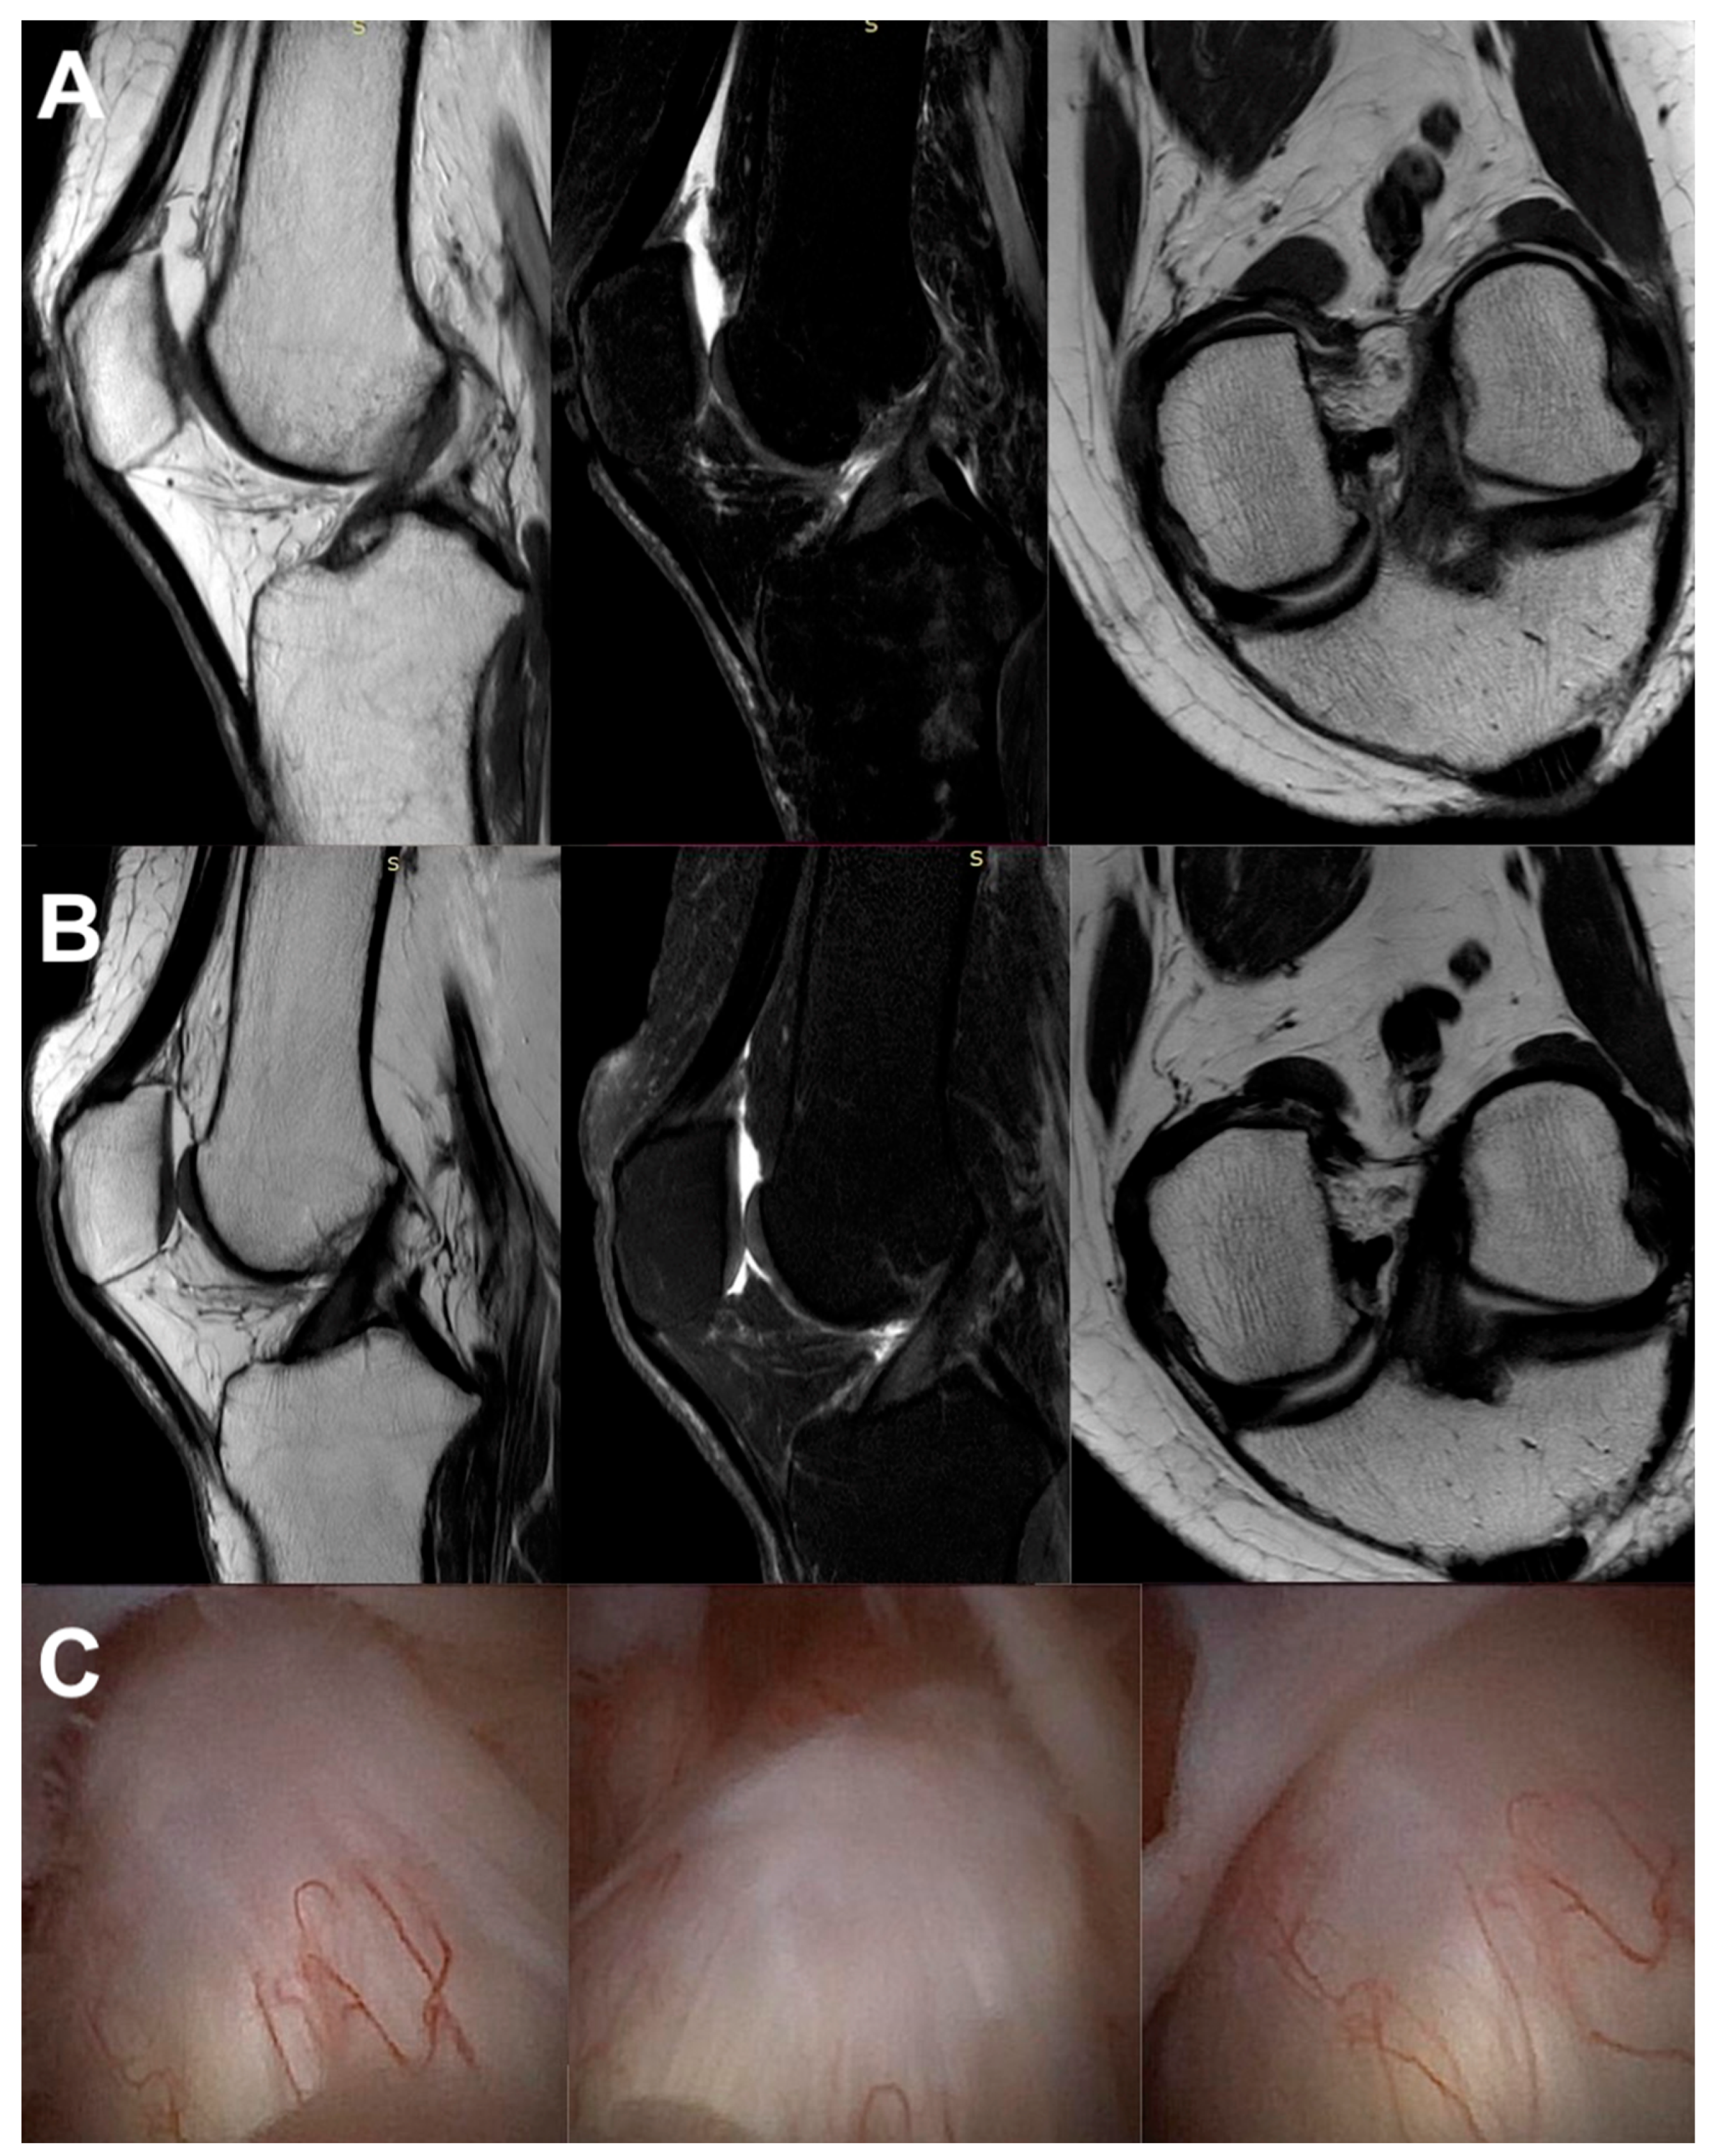

3.3. Imaging Analysis